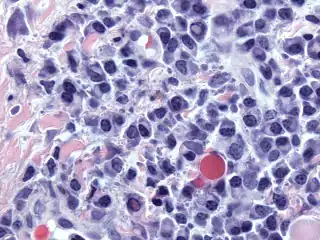

Bone marrow aspirate showing the histologic correlate of multiple myeloma under the microscope, H&E stain -

Plasmacytoma, H&E stain -

Histopathology

A bone marrow biopsy is usually performed to estimate the percentage of bone marrow occupied by plasma cells. This percentage is used in the diagnostic criteria for myeloma. Immunohistochemistry (staining particular cell types using antibodies against surface proteins) can detect plasma cells that express immunoglobulin in the cytoplasm and occasionally on the cell surface; myeloma cells are often CD56, CD38, CD138, and CD319 positive and CD19, CD20, and CD45 negative.[15] Flow cytometry is often used to establish the clonal nature of the plasma cells, which will generally express only kappa or lambda light chain. Cytogenetics may also be performed in myeloma for prognostic purposes, including a myeloma-specific fluorescent in situ hybridization and virtual karyotype.

The plasma cells seen in multiple myeloma have several possible morphologies. First, they could have the appearance of a normal plasma cell, a large cell two or three times the size of a peripheral lymphocyte. Because they are actively producing antibodies, the Golgi apparatus typically produces a light-colored area adjacent to the nucleus, called a perinuclear halo. The single nucleus (with inside a single nucleolus with vesicular nuclear chromatin) is eccentric, displaced by an abundant cytoplasm. Other common morphologies seen, but which are not usual in normal plasma cells, include:

- Bizarre cells, which are multinucleated

- Mott cells, containing multiple clustered cytoplasmic droplets or other inclusions (sometimes confused with auer rods, commonly seen in myeloid blasts)

- Flame cells, having a fiery red cytoplasm[43][44]